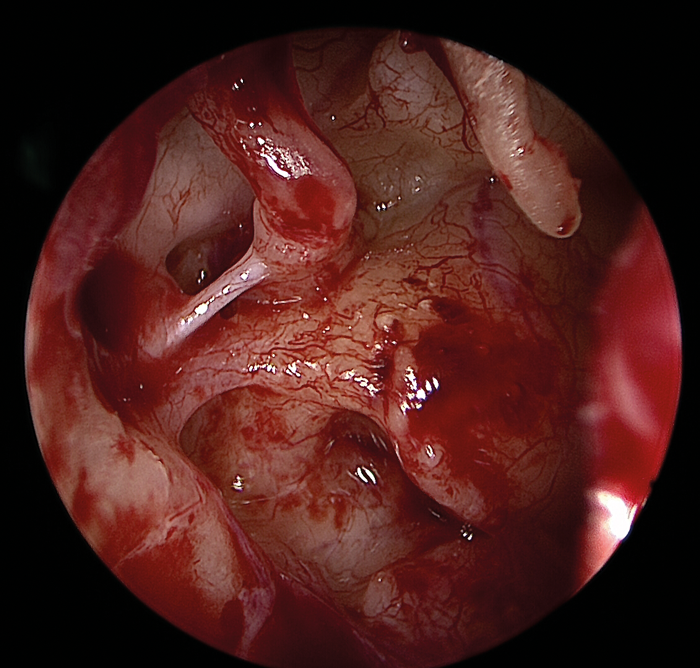

The greatest benefit of the endoscope lies in exposing previously hidden areas or blind spots such as the retrotympanum, hypotympanum, anterior mesotypanum, epitympanum and antrum (Figure 4).

Figure 4 (Top, middle and bottom): Endoscopic view of the middle ear with an intact ossicular chain.

The improved visualisation of hidden structures in a minimally invasive fashion results in a reduction in residual and recurrent disease rates [4,5], less postoperative pain, quicker recovery, no external incisions, no need for bulky mastoid dressings.